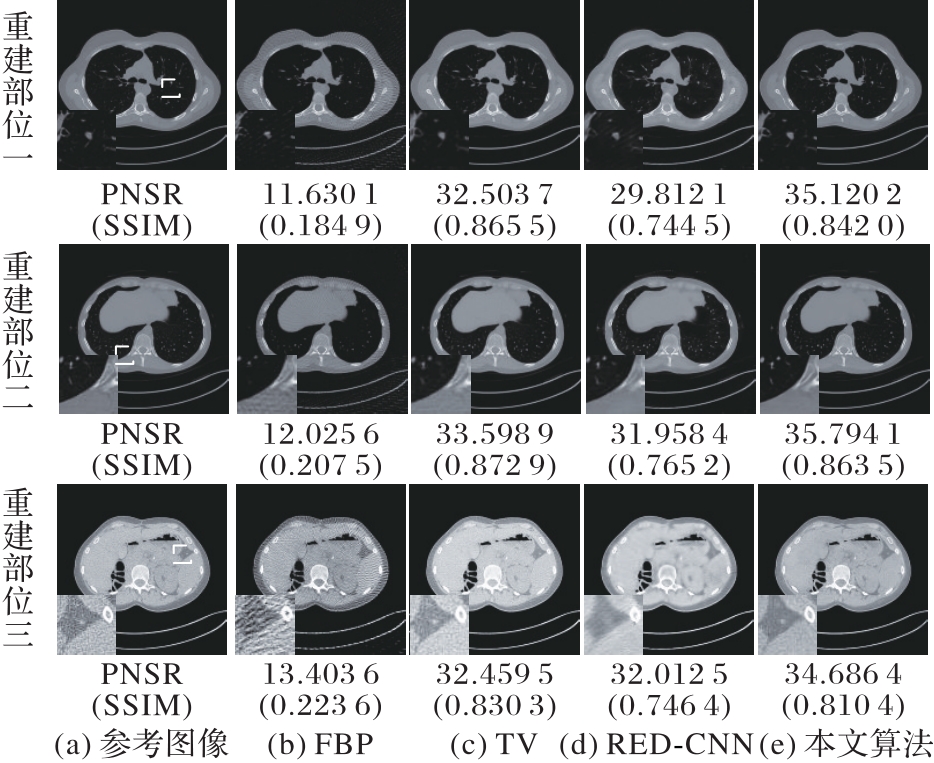

针对采用时域滤波器解析重建后图像存在伪影和图像细节丢失等问题,提出了一种基于卷积神经网络(CNN)的时频域计算机断层扫描(CT)重建算法。首先,在频域中构建了基于卷积神经网络的滤波器网络,实现投影数据的频域滤波;其次,利用反投影操作算子对频域滤波后结果进行域转换得到重建图像;接着,在图像域构建网络对来自反投影层的图像进行处理;最后,在采用最小均方误差损失函数基础上引入多尺度结构相似度损失函数组成复合损失函数,减轻神经网络对结果图像的模糊效应,保留重建图像细节。图像域网络和投影域滤波网络联合作用,最终得到重建结果。在临床数据集上验证了所提算法的有效性,相较于滤波反投影(FBP)算法、全变分(TV)算法及图像域残差编解码CNN(RED-CNN)算法,当投影数目分别为180和90时,所提算法重建结果图像信噪比(PSNR)和结构相似度(SSIM)最高,且归一化均方根误差(NMSE)最小;当投影数目为360时,所提算法仅次于TV算法。实验结果表明,所提算法可以提高CT图像重建图像质量,是一种可行且有效的方法。

| 算法 | 投影数目为360 | 投影数目为180 | 投影数目为90 | ||||||

| PSNR/dB | SSIM | NMSE | PSNR/dB | SSIM | NMSE | PSNR/dB | SSIM | NMSE | |

| FBP | 15.167 9±0.801 9 | 0.277 0±0.016 0 | 0.721 9±0.218 7 | 12.126 7±0.601 2 | 0.200 2±0.014 4 | 1.441 9±0.397 0 | 9.468 6±0.539 0 | 0.147 2±0.015 3 | 2.643 6±0.703 1 |

| TV | 35.954 3±1.207 5 | 0.889 5±0.013 6 | 0.005 9±0.001 4 | 32.259 1±1.408 6 | 0.835 2±0.018 5 | 0.013 9±0.004 2 | 26.268 6±1.352 7 | 0.732 4±0.021 5 | 0.055 8±0.017 8 |

| RED-CNN | 34.176 9±1.146 1 | 0.827 9±0.022 8 | 0.009 0±0.003 0 | 31.347 0±0.628 7 | 0.738 3±0.013 1 | 0.017 3±0.004 8 | 28.944 5±1.800 8 | 0.661 9±0.045 5 | 0.034 4±0.034 7 |

| 本文算法 | 35.505 9±1.129 3 | 0.865 4±0.020 7 | 0.006 5±0.001 6 | 34.267 1±0.779 4 | 0.845 4±0.025 2 | 0.008 7±0.002 3 | 32.119 3±0.677 4 | 0.770 8±0.022 8 | 0.014 2±0.003 3 |

表2 不同算法测试集上指标对比

Tab. 2 Index comparison of different comparison algorithms under different projections